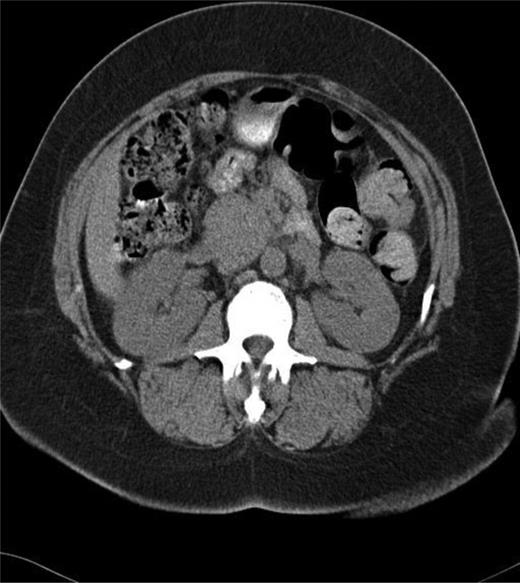

The patient is a 58-year-old African-American female who presented with several months of left lower quadrant pain. A computed tomography (CT) and magnetic resource imaging (MRI) of abdomen/pelvis demonstrated a 3.8-cm hyper vascular mass in the head of the pancreas without any evidence of distant metastasis or spread to the surrounding vasculature (Figs. 1 and 2). The differential diagnosis includes endocrine tumor, gastrointestinal stromal tumor, sarcoma, solid pseudo-papillary tumor, inflammatory pseudotumour/tumor forming autoimmune pancreatitis and SFT. An endoscopic ultrasound with fine-needle aspiration was nondiagnostic. The carcinoembryonic antigen (CEA) and cancer antigen 19-9 (CA 19-9) were both mildly elevated at 6.5 (nl range 0–5.0) and 39 (nl range 0–37), respectively. Functional endocrine hormone studies were significant only for a mildly elevated gastrin level of 214, but the insulin, glucagon and vasoactive intestinal peptide (VIP) levels were all within normal limits. Her review of symptoms was negative for jaundice or weight loss. A Whipple procedure was performed. The patient had an uncomplicated hospital course and was discharged Post-op Day 7. She is alive and well 2 years post-operatively.

CT of the abdomen and pelvis showing mass in head of the pancreas.